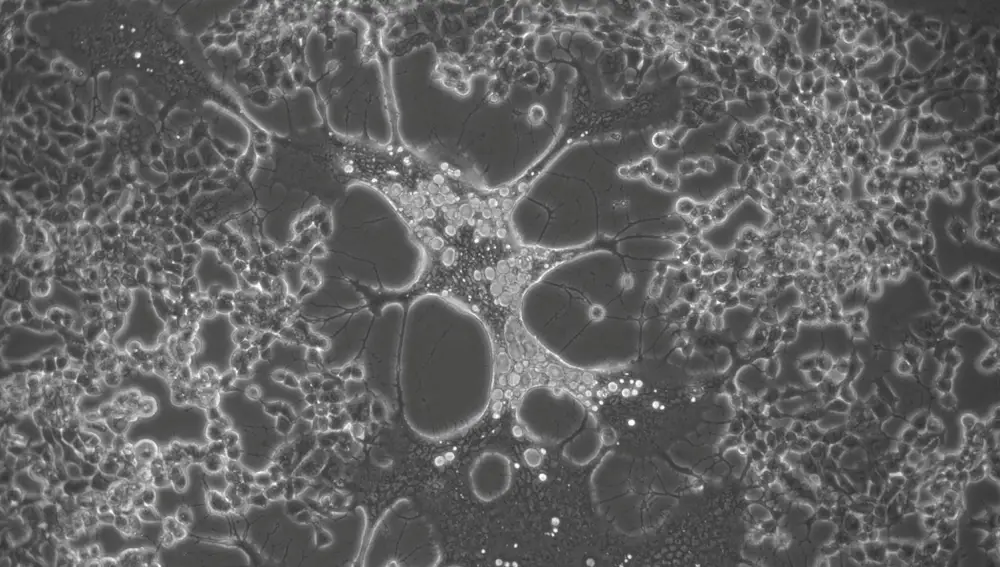

5. Virus del herpes, la nueva esperanza contra el cáncer

Aunque la pandemia de la Covid-19 ha copado todos los titulares de los últimos dos años, el cáncer sigue siendo una de las enfermedades a la que más recursos de investigación se dedica. La Ciencia no ceja en el empeño de dar con nuevas herramientas que puedan ayudar en la lucha contra el cáncer, convertida en una de las patologías que mayor mortalidad provoca en nuestro país. Ahora,investigadores del Instituto Fraunhofer de Ingeniería Interfacial y Biotecnología IGB (Alemania) han conseguido modificar genéticamente el virus del herpes simple tipo 1, que provoca el doloroso herpes labial, de tal manera que en el futuro podrá utilizarse en la lucha contra el cáncer.